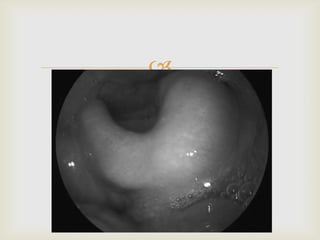

 DIAGNOSIS:

 “CHERRY RED”APPEARANCE OF EPIGLOTTIS ON

LARYNGOSCOPY